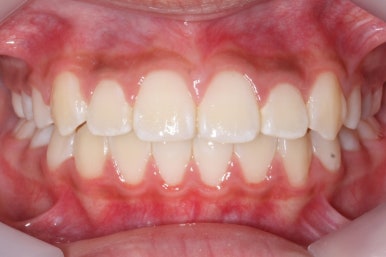

치열이 매우 가지런해졌죠. 이 후에는 특이사항 없이 종료가 되었습니다.

미소를 짓거나 웃는 모습이 확연히 좋아졌습니다.

덧니가 없어져서 그런지 입술 다문 모습도 편안함이 느껴지네요. 턱끝의 쭈글한 주름도 없어졌습니다.

이 정도면 비발치 연산동덧니교정으로도 충분히 좋았던 효과를 보았습니다.

연산동덧니교정을 하고자 키다리아저씨치과에 처음 내원했을 때와 개선이 된 후의 비교 모습입니다. 영구치가 모두 나왔고 덧니가 개선이 된 후에 마무리가 되었습니다.